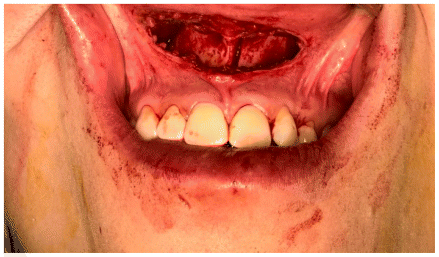

The surgical procedure was performed following minimally invasive orthognathic surgery, involving a mucoperiosteal incision in the anterior vestibular region of the maxilla. The surgical access measured approximately 2 cm, extending from one central incisor to the other. (Figure 4)

A subperiosteal dissection was performed in the nasomaxillary region, followed by the creation of a myomucosal tunnel in the posterior area of the maxilla to facilitate the passage of the implant. (Figure 5)